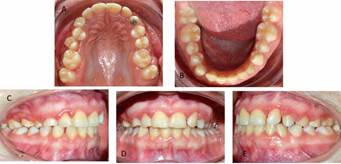

La planificación del tratamiento de Ortodoncia comprendió un tratamiento bimaxilar de compromiso con exodoncias de los dientes 1.3 - 6.3 y 8.3. El plan de tratamiento inicial comenzó con el uso de aparatología Multibrackets MBT .022 con bandas en molares superiores e inferiores. La paciente no consentía sesiones de más de 15 minutos, realizando la instalación parcial superior, a modo de adaptación al tratamiento de ortodoncia, para posteriormente continuar con instalación de arcada inferior. Se derivó a Odontopediatría para las exodoncias de los dientes 1.3 - 6.3 y 8.3. Luego de cuatro meses, la cuidadora refiere que la paciente descementaba intencionalmente los brackets con un lápiz. Si bien se realizó la reposición de éstos, el mal hábito persistió, por lo que se adoptó como alternativa de tratamiento instalar botones, con el objetivo de generar cupla y desrotar los incisivos superiores, continuando con la etapa de alineación y nivelación (figura 4). El mal comportamiento de la paciente persistió en el tiempo, pero aun cuando tenía indicación de retiro de los aparatos, debido a su conducta y la permanente gingivitis, se determinó modificar los objetivos terapéuticos propuestos en un inicio del tratamiento, dando prioridad a lograr el cierre del espacio provocado por la exodoncia del diente 6.3 para la alineación de la arcada superior. Por ellos, se suspendió la instalación de brackets en la arcada inferior y se decidió confeccionar bandas individuales para los dientes que requerían mayor alineación, utilizando como secuencia de arco un Niti Natural .014 y .020, junto con un SS .020 (Figura 5)

Una vez conseguida la alineación y nivelación del arco superior, se cerraron los espacios mediante cadena elastomérica. Al alcanzar el cierre del espacio superior, se realizó el retiro de los aparatos superiores, permaneciendo un pequeño diastema entre los dientes 4.2 y 4.3. La fase activa del tratamiento de ortodoncia duró 22 meses. Como contención se empleó una placa Hawley simple (Figura 6). Al control a los seis meses posterior al retiro de los aparatos, se observan pequeños diastemas en la zona entre los dientes 2.2 y 2.3, junto con las rotaciones de los premolares 1.4 y 1.5 (Figura 7). La paciente no permitió el retiro del botón palatino del diente 2.3, el que debió ser desgastado con instrumental rotatorio. A pesar de los desafíos que fueron presentándose durante el tratamiento, se advierte una mejoría en la alineación dentaria ligado a una oclusión estable.